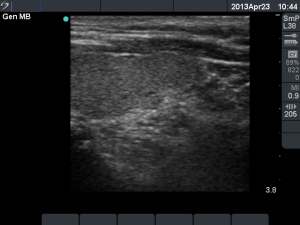

Second session (second row of images):

Clinical presentation: the patient became aware of mild neck discomfort lasting for 2 days.

I removed 3.5 ml serous-watery fluid and administered 1.5 mL ethanol.